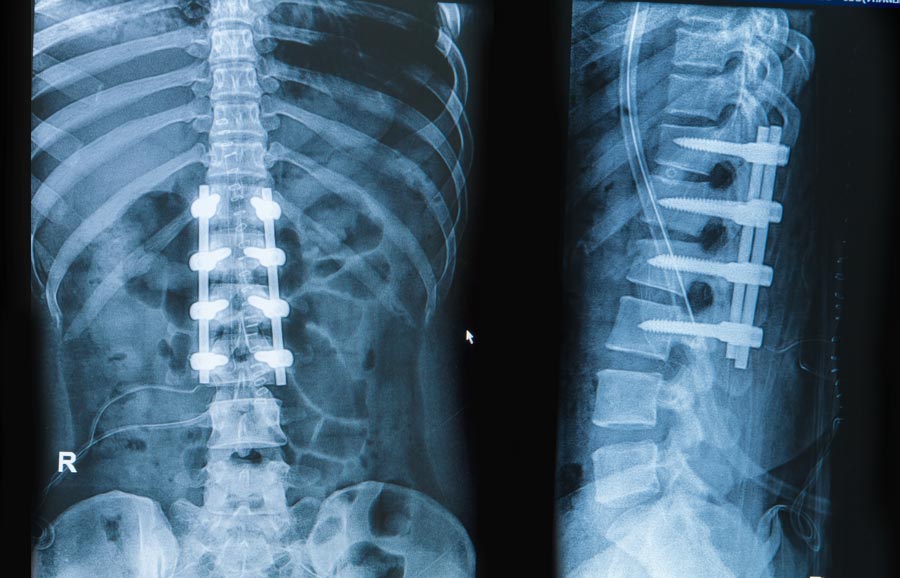

- Now, an incision (cut on the skin) is made at the site of fusion to place the bone graft.

- Upon placing the bone graft between the vertebrae, the surgeon may place screws, plates or rods to hold the spine still. Finally, once the procedure is done the surgeon will close the incision with stitches or staples.